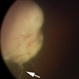

Choroidal Melanoma With Vitreous Seeding

Choroidal Melanoma

Underlying retinal choroidal melanoma with dense vitreous seeding of choroidal melanoma cells.